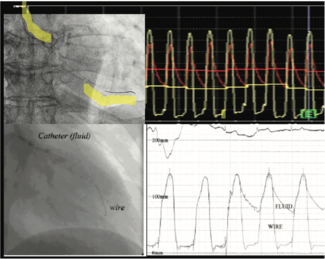

Ziad A. Ali, MD, DPhil; Allen Jeremias, MD, MSc

Doing an iFR pullback identifies the physiologic impact of the distribution pattern of atherosclerosis in a particular vessel. We have a road map so we know where the lesions are. It is not adding a lot of time, but it adds accuracy to the...